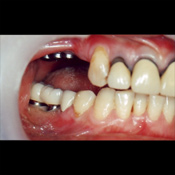

装着前の口腔内の様子

左右下の奥歯に上部構造(セラミッククラウン)を装着した写真です。